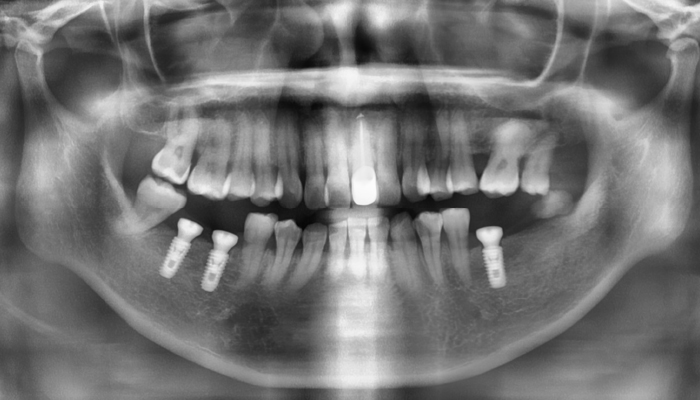

• 식립 전

식립 후